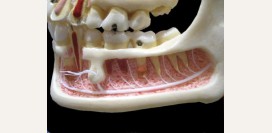

Анатомическое строение зуба

- коронка – часть зуба, которая выступает над десной и принимает непосредственное участие в обеспечении функций

- шейка – место перехода коронки в корень

- корень – часть зуба, которая находится в лунке, у зуба может быть 1, 2 или 3 корня

- верхушка зуба – конечная часть корня зуба

Поверхности, которые имеет коронка зуба:

- вестибулярная поверхность – обращена вперед, у резцов и клыков соприкасается со слизистой оболочкой губ, а у моляров и премоляров – со слизистой оболочкой щек;

- язычная поверхность – обращена в сторону ротовой полости;

- поверхность смыкания – обращена в сторону зубов, расположенных на противоположной стороне (поверхности, которыми верхние зубы смыкаются с нижними);

- контактные поверхности – это боковые поверхности коронки зуба, которые смыкаются с соседними зубами.